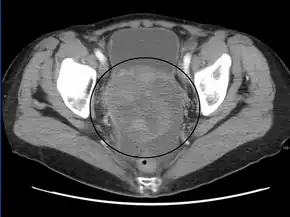

A very large ovarian cancer as seen on CT

CT scanning is preferred to assess the extent of the tumor in the abdominopelvic cavity, though magnetic resonance imaging can also be used.[21] CT scanning can also be useful for finding omental caking or differentiating fluid from solid tumor in the abdomen, especially in low malignant potential tumors. However, it may not detect smaller tumors. Sometimes, a chest x-ray is used to detect metastases in the chest or pleural effusion. Another test for metastatic disease, though it is infrequently used, is a barium enema, which can show if the rectosigmoid colon is involved in the disease. Positron emission tomography, bone scans, and paracentesis are of limited use; in fact, paracentesis can cause metastases to form at the needle insertion site and may not provide useful results.[22] However, paracentesis can be used in cases where there is no pelvic mass and ascites is still present.[22] A physician suspecting ovarian cancer may also perform mammography or an endometrial biopsy (in the case of abnormal bleeding) to assess the possibility of breast malignancies and endometrial malignancy, respectively. Vaginal ultrasonography is often the first-line imaging study performed when an adnexal mass is found. Several characteristics of an adnexal mass indicate ovarian malignancy; they usually are solid, irregular, multilocular, and/or large; and they typically have papillary features, central vessels, and/or irregular internal septations.[24] However, SCST has no definitive characteristics on radiographic study.[25]